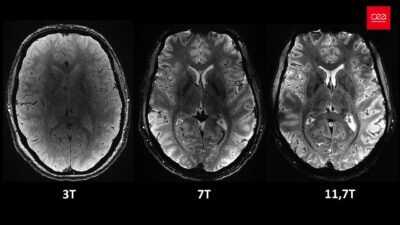

L’IRM à 7 teslas est une technologie d’imagerie ultra-haut champ, qui permet d’obtenir une résolution et un contraste bien supérieurs à ceux des IRM classiques (1,5 ou 3T), utilisées couramment à l’hôpital.

- Visualiser des détails très fins du cerveau, jusque-là invisibles,

- Mieux détecter des anomalies structurelles comme de petites malformations corticales ou des lésions microscopiques,

- Étudier la vascularisation cérébrale et le métabolisme du cerveau avec une précision inédite,

«L’IRM 7T nous permet de voir ce que l’IRM 3T ne montre pas : les micro-anomalies, la vascularisation fine, le métabolisme cérébral… Ce niveau de détail change notre manière de comprendre et d’aborder les pathologies de l’enfant.»

Crédit images : CEA/Neurospin